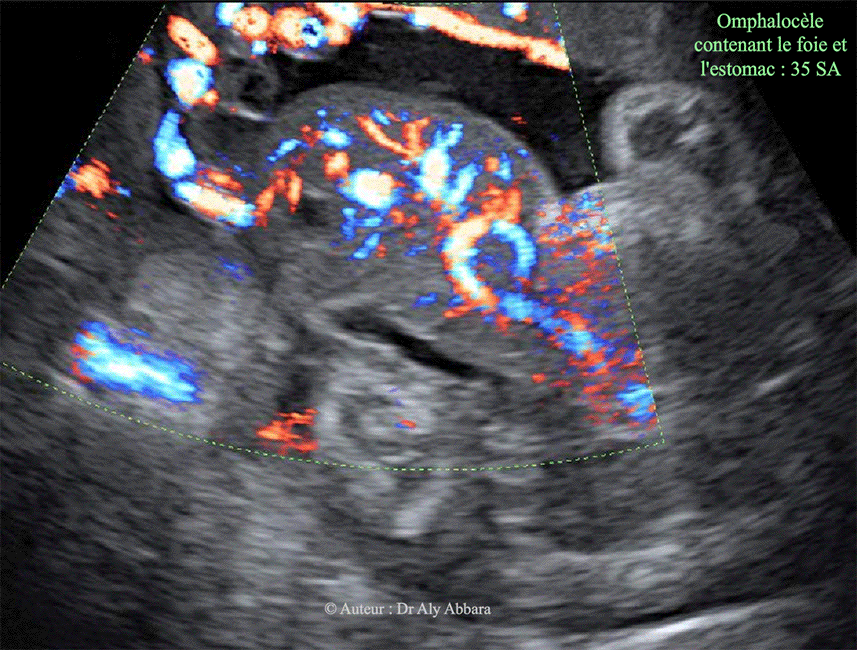

Omphalocèle - Grossesse de 35 SA

Image échographique montrant une grossesse de 35 SA caractérisée par la présence d'une volumineuse omphalocèle contenant la totalité du foie et sa vésicule biliaire, puis l'estomac. L'insertion du cordon ombilical se situe sur la surface extérieure l'omphalocèle. La veine ombilicale traverse le foie. Aucune anomalie morphologique associée et décelable à l'échographie. Le caryotype fœtal ne montre pas d'anomalie chromosomique associée (46, XX).